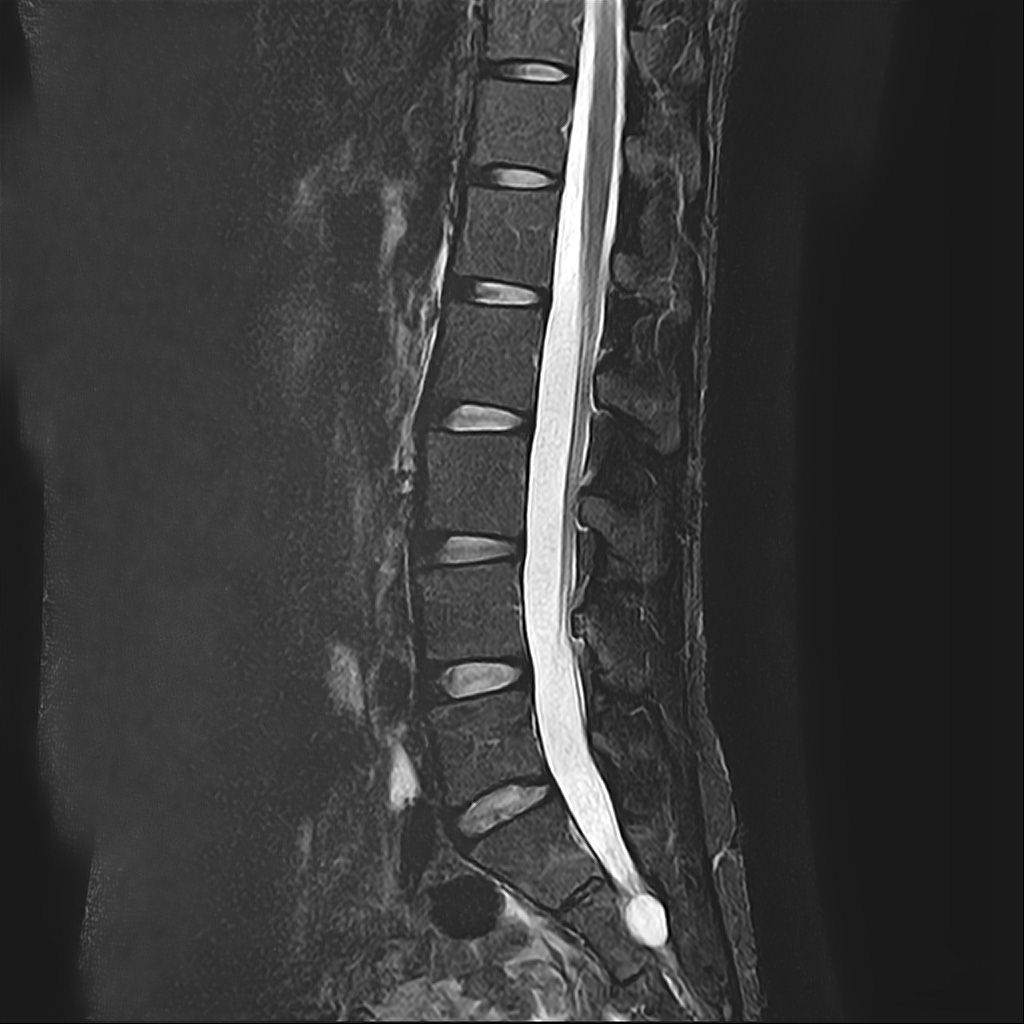

낭종s1-3번까지 꼬리뼈쪽으로 크게 나있다고했고, 단면상으로는 s2,3번이 촬영이 안되서 확인이안된다합니다. 허리디스크가 미약하게 4,5번에 있다고 했는데,

혹시 디스크로 인한 신경눌림인지, 낭종으로 인한건지 알수잇나요?